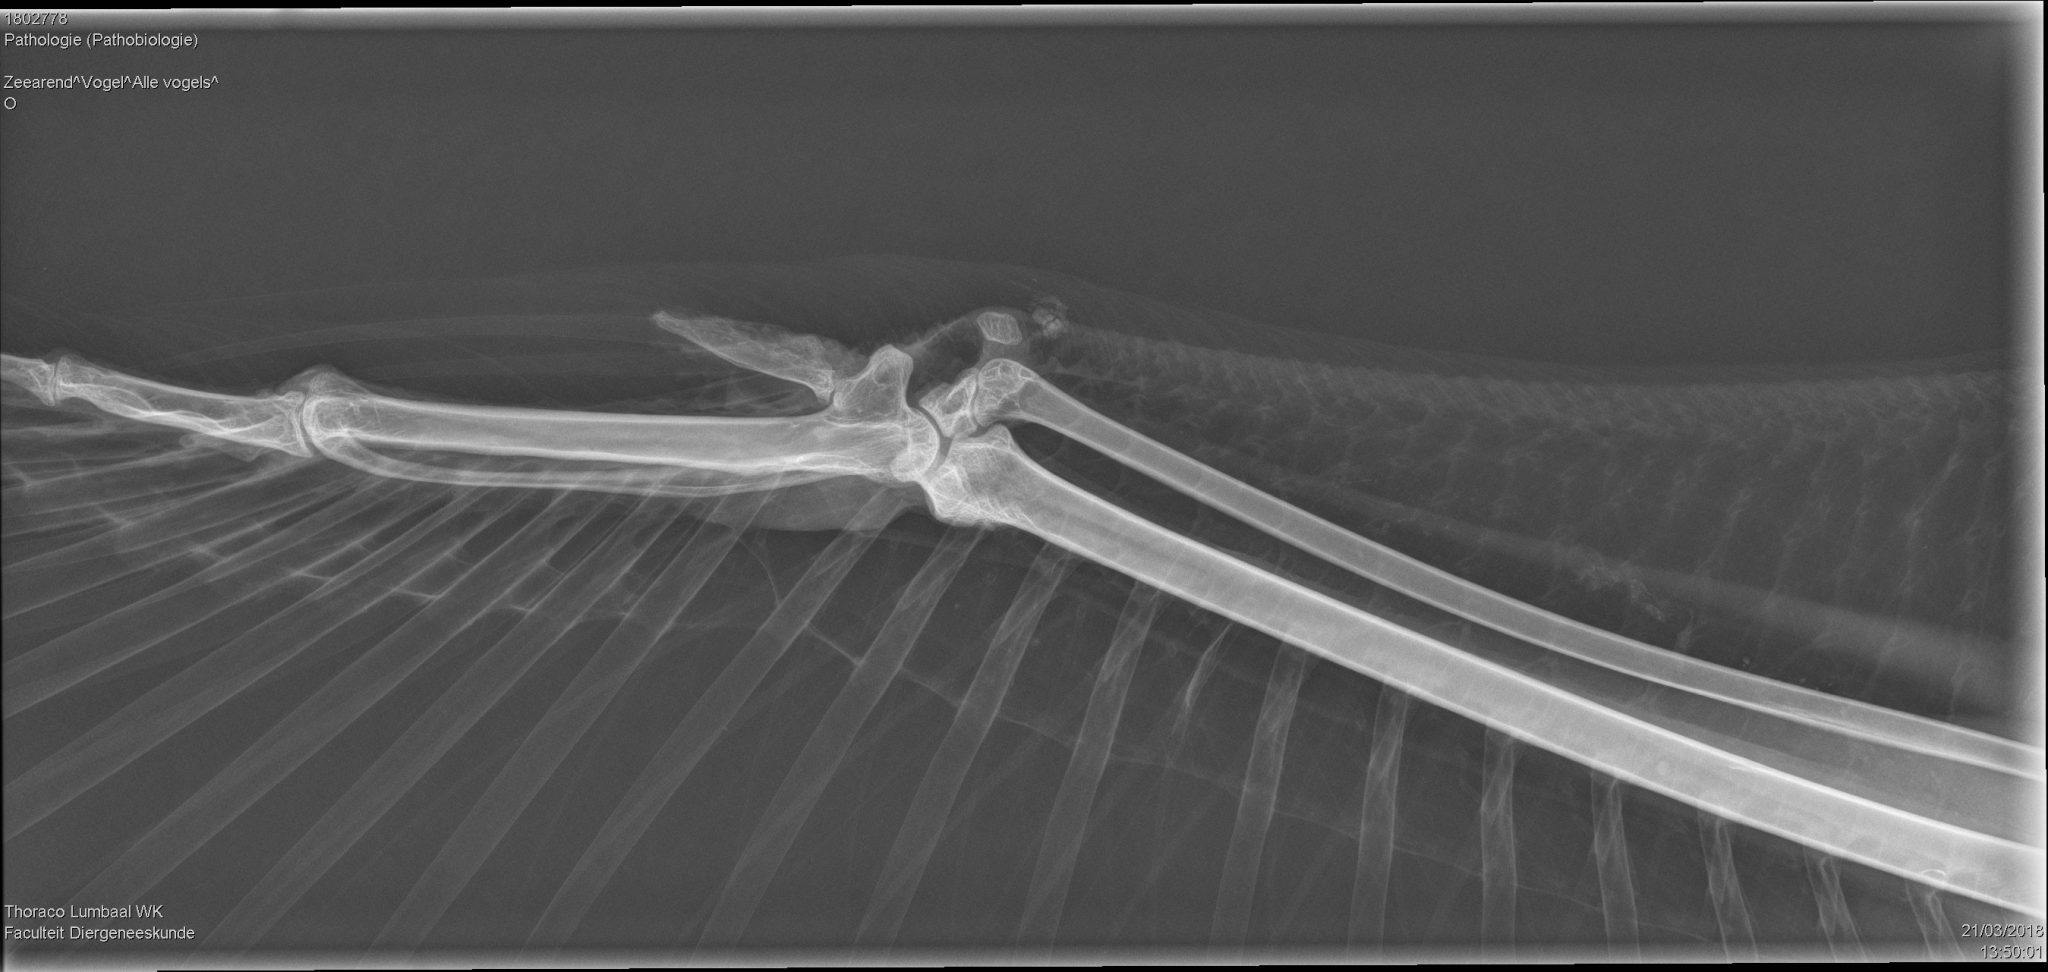

On arrival at the faculty the sea eagle was first delivered to the diagnostic imaging department where radiographs and a CT scan were performed – a first in the Netherlands! These images showed multiple breaks including a complicated fracture of the metacarpal of the left wing and a distal fracture of the left metatarsal. The middle digit of the right foot had been crushed.

| Radiographs of the left wing showing the broken metacarpus and of the right wing which was intact | |

| Foto’s: Afdeling Diagnostische Beeldvorming, Faculteit Diergeneeskunde, Universiteit Utrecht | |